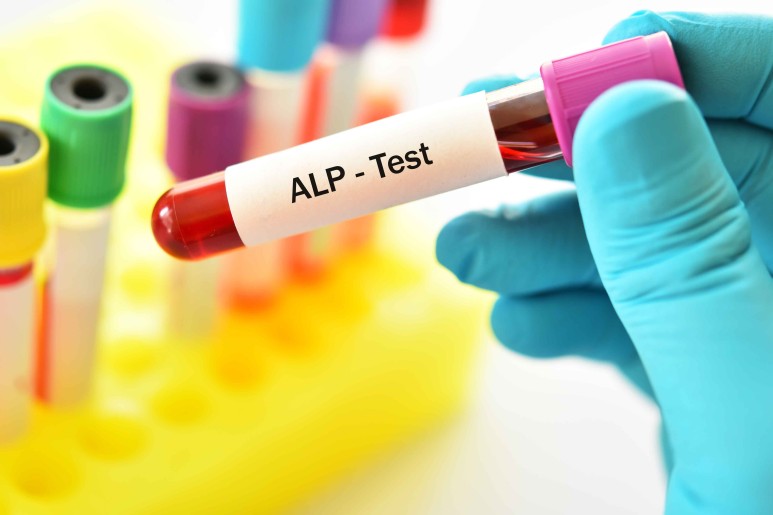

ALP

또한 간에서 합성이 증가하면 알칼리성 인산분해효소도 상승할 수 있습니다.

알칼리성 인산분해효소 수치는 담관 폐쇄 시 빌리루빈 수치 상승보다 빠르게 발생합니다.그 밖에도 아미노 전이 효소, 감마 글루타밀 전이 효소의 상승도 동반합니다.

담관이 어느 정도 막혀도 알칼리성 인산분해효소가 상승하기 때문에

더욱이 담관 70% 이상 폐쇄 시 상승하는 빌리루빈은 담관 폐쇄를 알 수 있는 가장 민감한 검사입니다.